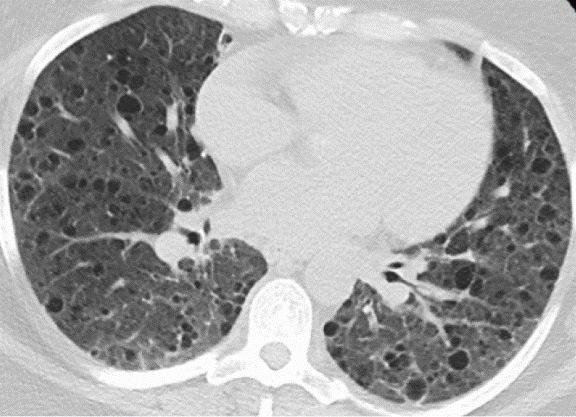

比如淋巴管肌瘤病(LAM),下图是典型影像,呈现弥漫性的薄壁囊肿,病变分布得非常均匀、大小相似:

还可能合并一些肺外表现(如可能会有脑部的改变),但无论有没有结节性硬化症、是散发的还是遗传的,患者都有可能出现有肾脏病变,这点需要注意。

图:淋巴管肌瘤病,TSC相关(结节性硬化症,一种多系统表现的肿瘤性遗传病)